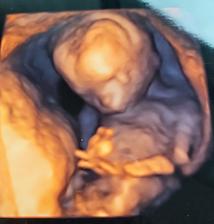

Druhé šťastie